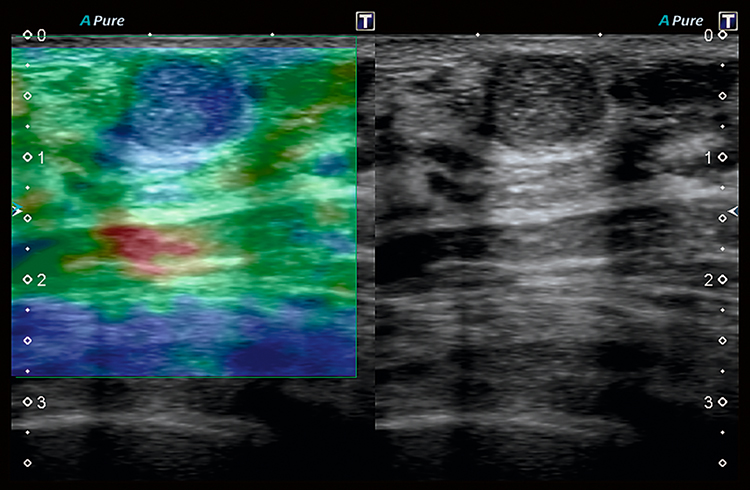

- Улучшенный динамический поток Advanced Dynamic Flow (ADF) – запатентованная технология Toshiba, обеспечивающая высокое разрешение при цветовом доплеровском сканировании.

- Компрессионная эластография – классический метод раннего выявления опухолей.

- Эластография сдвиговой волны – новейший метод, позволяющий обнаружить опухоли при помощи определения скорости движения волн.

Технология визуализации микроциркуляторного русла (SMI), разработанная корпорацией Canon Medical Systems, расширяет диагностические возможности ультразвуковых систем Aplio. Позволяет визуализировать низкоскоростной кровоток в микрососудах.

Технология сдвиговых волн Canon Medical Systems обеспечивает количественное измерение и динамическое визуальное отображение жесткости ткани в различных клинических условиях, начиная от брюшной полости и заканчивая исследованиями мелких деталей. Высокоточный и воспроизводимый инструмент обеспечивает полностью интегрированные измерения и отчеты для полной интеграции в ваш клинический рабочий процесс.

Технология эластографии с функцией сохранения исходных данных в формате RAW предназначена для локализации и оценки жесткости пальпируемых образований с непревзойденной точностью.

Эластография в реальном времени. Наше комплексное решение для эластографии с функциональностью необработанных данных помогает локализовать и оценивать ощутимые массы с высокой точностью, чувствительностью и воспроизводимостью в широком диапазоне клинических условий. Различные параметры эластичности ткани могут быть определены количественно или иметь цветовую кодировку на параметрических изображениях, делая подозрительные изменения ткани количественными и видимыми на ультразвуковом изображении.

Индикатор качества помогает вам правильно подать давление на датчик, гарантируя, что вы всегда получаете надежные результаты.